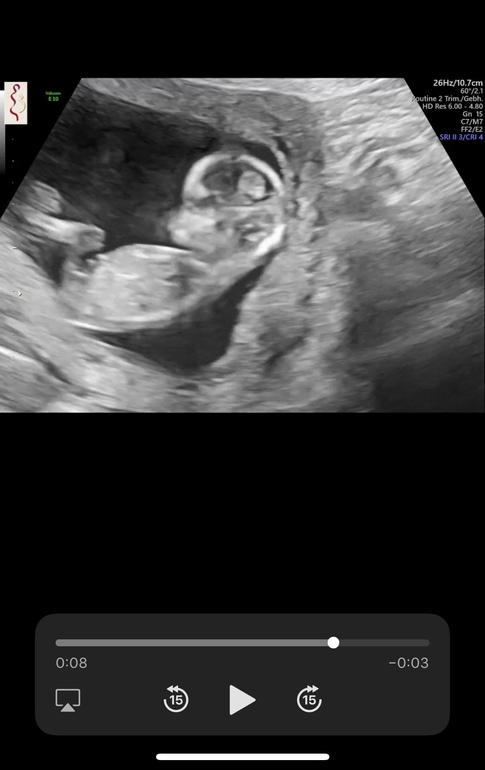

Результаты: УЗИ, КТГ, доплера, скринингаЗнаю, что рано! знаю,что всёравно что на кофейной гуще! Но, блин и я туда же 🙈😅 все кидают свои узи и девочки как-то там что-то видят и я вас поспамлю😅

12+2🙈

Пару фоток, есть видео, вроде вырезала все моменты, когда самое «интересное видно»🙈

Лобастый как мальчик, а пипку не вижу, но это фото такое... А по форме головы не 100%говорят,хотя у всех моих мальчишек на узи, головы были с крутым лобиком а у доченьки аккуратная, ровненькая...